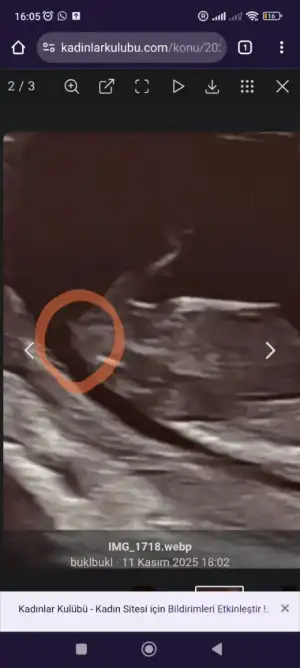

Ben de çok anlamıyorum ama yine de tahminde bulunacağım. Erkek gibi geldi 😊

• Screenshot_2025-11-11-16-05-41-591-edit_com.android.chrome.webp

Screenshot_2025-11-11-16-05-41-591-edit_com.android.chrome.webp

17 KB · Görüntüleme: 25